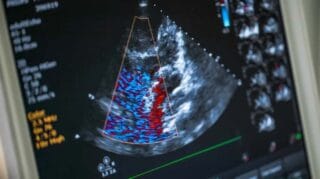

یکی از ویژگیهای مهم اکوکاردیوگرافی داپلر رنگی، توانایی تشخیص جریان خون درون قلب و عروق بهصورت رنگی است. در این روش، جریان خون قرمز و آبی نمایش داده میشود؛ رنگ قرمز نمایانگر جریان خون به سمت پروب دستگاه و رنگ آبی نمایانگر جریان دور از پروب است. این قابلیت به پزشک کمک میکند تا انواع اختلالات دریچههای قلب، گرفتگی عروق و مشکلات عروقی دیگر را بهدقت شناسایی کند.

اکوکاردیوگرافی داپلر رنگی جریان خون را در قلب و عروق با استفاده از کدهای رنگی نمایش میدهد. در این تصویرها، رنگ قرمز معمولاً نمایانگر جریان خونی است که به سمت پروب دستگاه در حرکت است و رنگ آبی نشاندهنده جریان خون دور شونده از پروب است. با این تفاوت رنگی، پزشک میتواند به آسانی اختلالات جریان خون مانند نارسایی دریچهها، گرفتگی عروق و نشتی خون در قلب را مشاهده و تشخیص دهد.